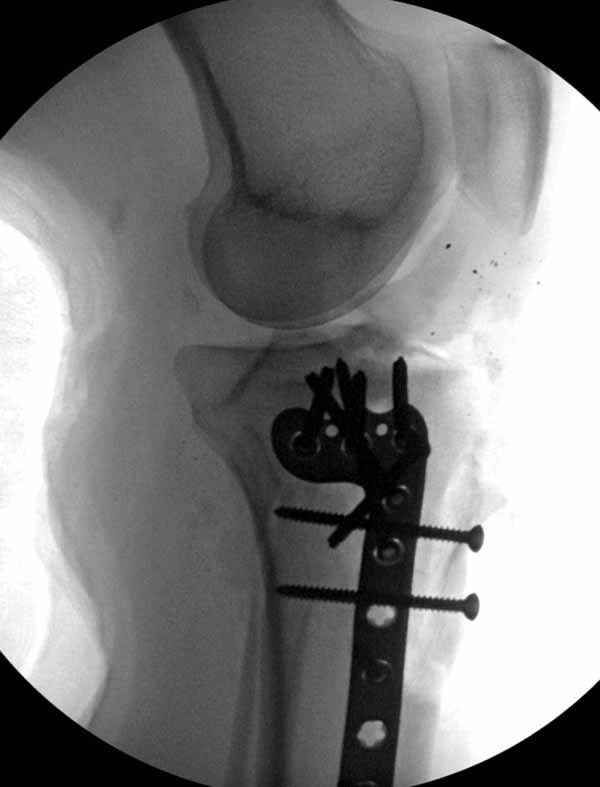

Больная Л., 23 года. Из анамнеза:со слов больной в 2006 г. появились боли правой н/конечности, обратилась поместу жительства к хирургу, было выполнена МРТ поясничного отдела позвоночника,назначено физиолечение. Через 2 месяца боли прекратились, через 4 месяца рецидив болевого синдрома. С 2006 – 2010 проводилось консервативное лечение по поводу остеохондроза поясничного отдела позвоночника. В октябре 2010 г. боли усилились. Выполнены Ro и КТ правого тазобедренного сустава, выявлен очаг патологической перестройки. Была направлена на консультацию в УНИИТО. В УНИИТО виюне 2011 г. поставлен дифференциальный диагноз между фибромой, солитарной костнойкистой и гигантоклеточной опухолью.

Клиника и течение заболевания похожи на однокамерную кисту. Больная молодая, желательно сохранить собственную головку. Надо спешить с операцией, иначе скоро произойдет перелом через тонкую стенку. Во время операции внутри будет пустота и небольшое количество жидкой крови.

Из всех перечисленных методов подходит вариант пластики аутокостью и усиление (арматура) шурупами. Основная задача сохранить интактную медиальную стенку и латеральный кортекс. Доступ передне-латеральный, но надо работать спереди шейки через небольшое окно в 10-15 мм. Фиксацию надо проводить между медиальной тонкой стенкой головки и латеральным кортексом. Каннюлированные шурупы 6.5 мм очень грубые и могут разрушить остаток стенки. Фиксировать надо кортикальными шурупами 3.5 мм, которые создадут мостик и арматуру в шейке. Провести по периметру шейки 4, и в центре пару шурупов. Во время операции и при манипуляции соблюдать осторожность, в любой момент может наступить стресс перелом. Заранее надо заказывать длинные шурупы!